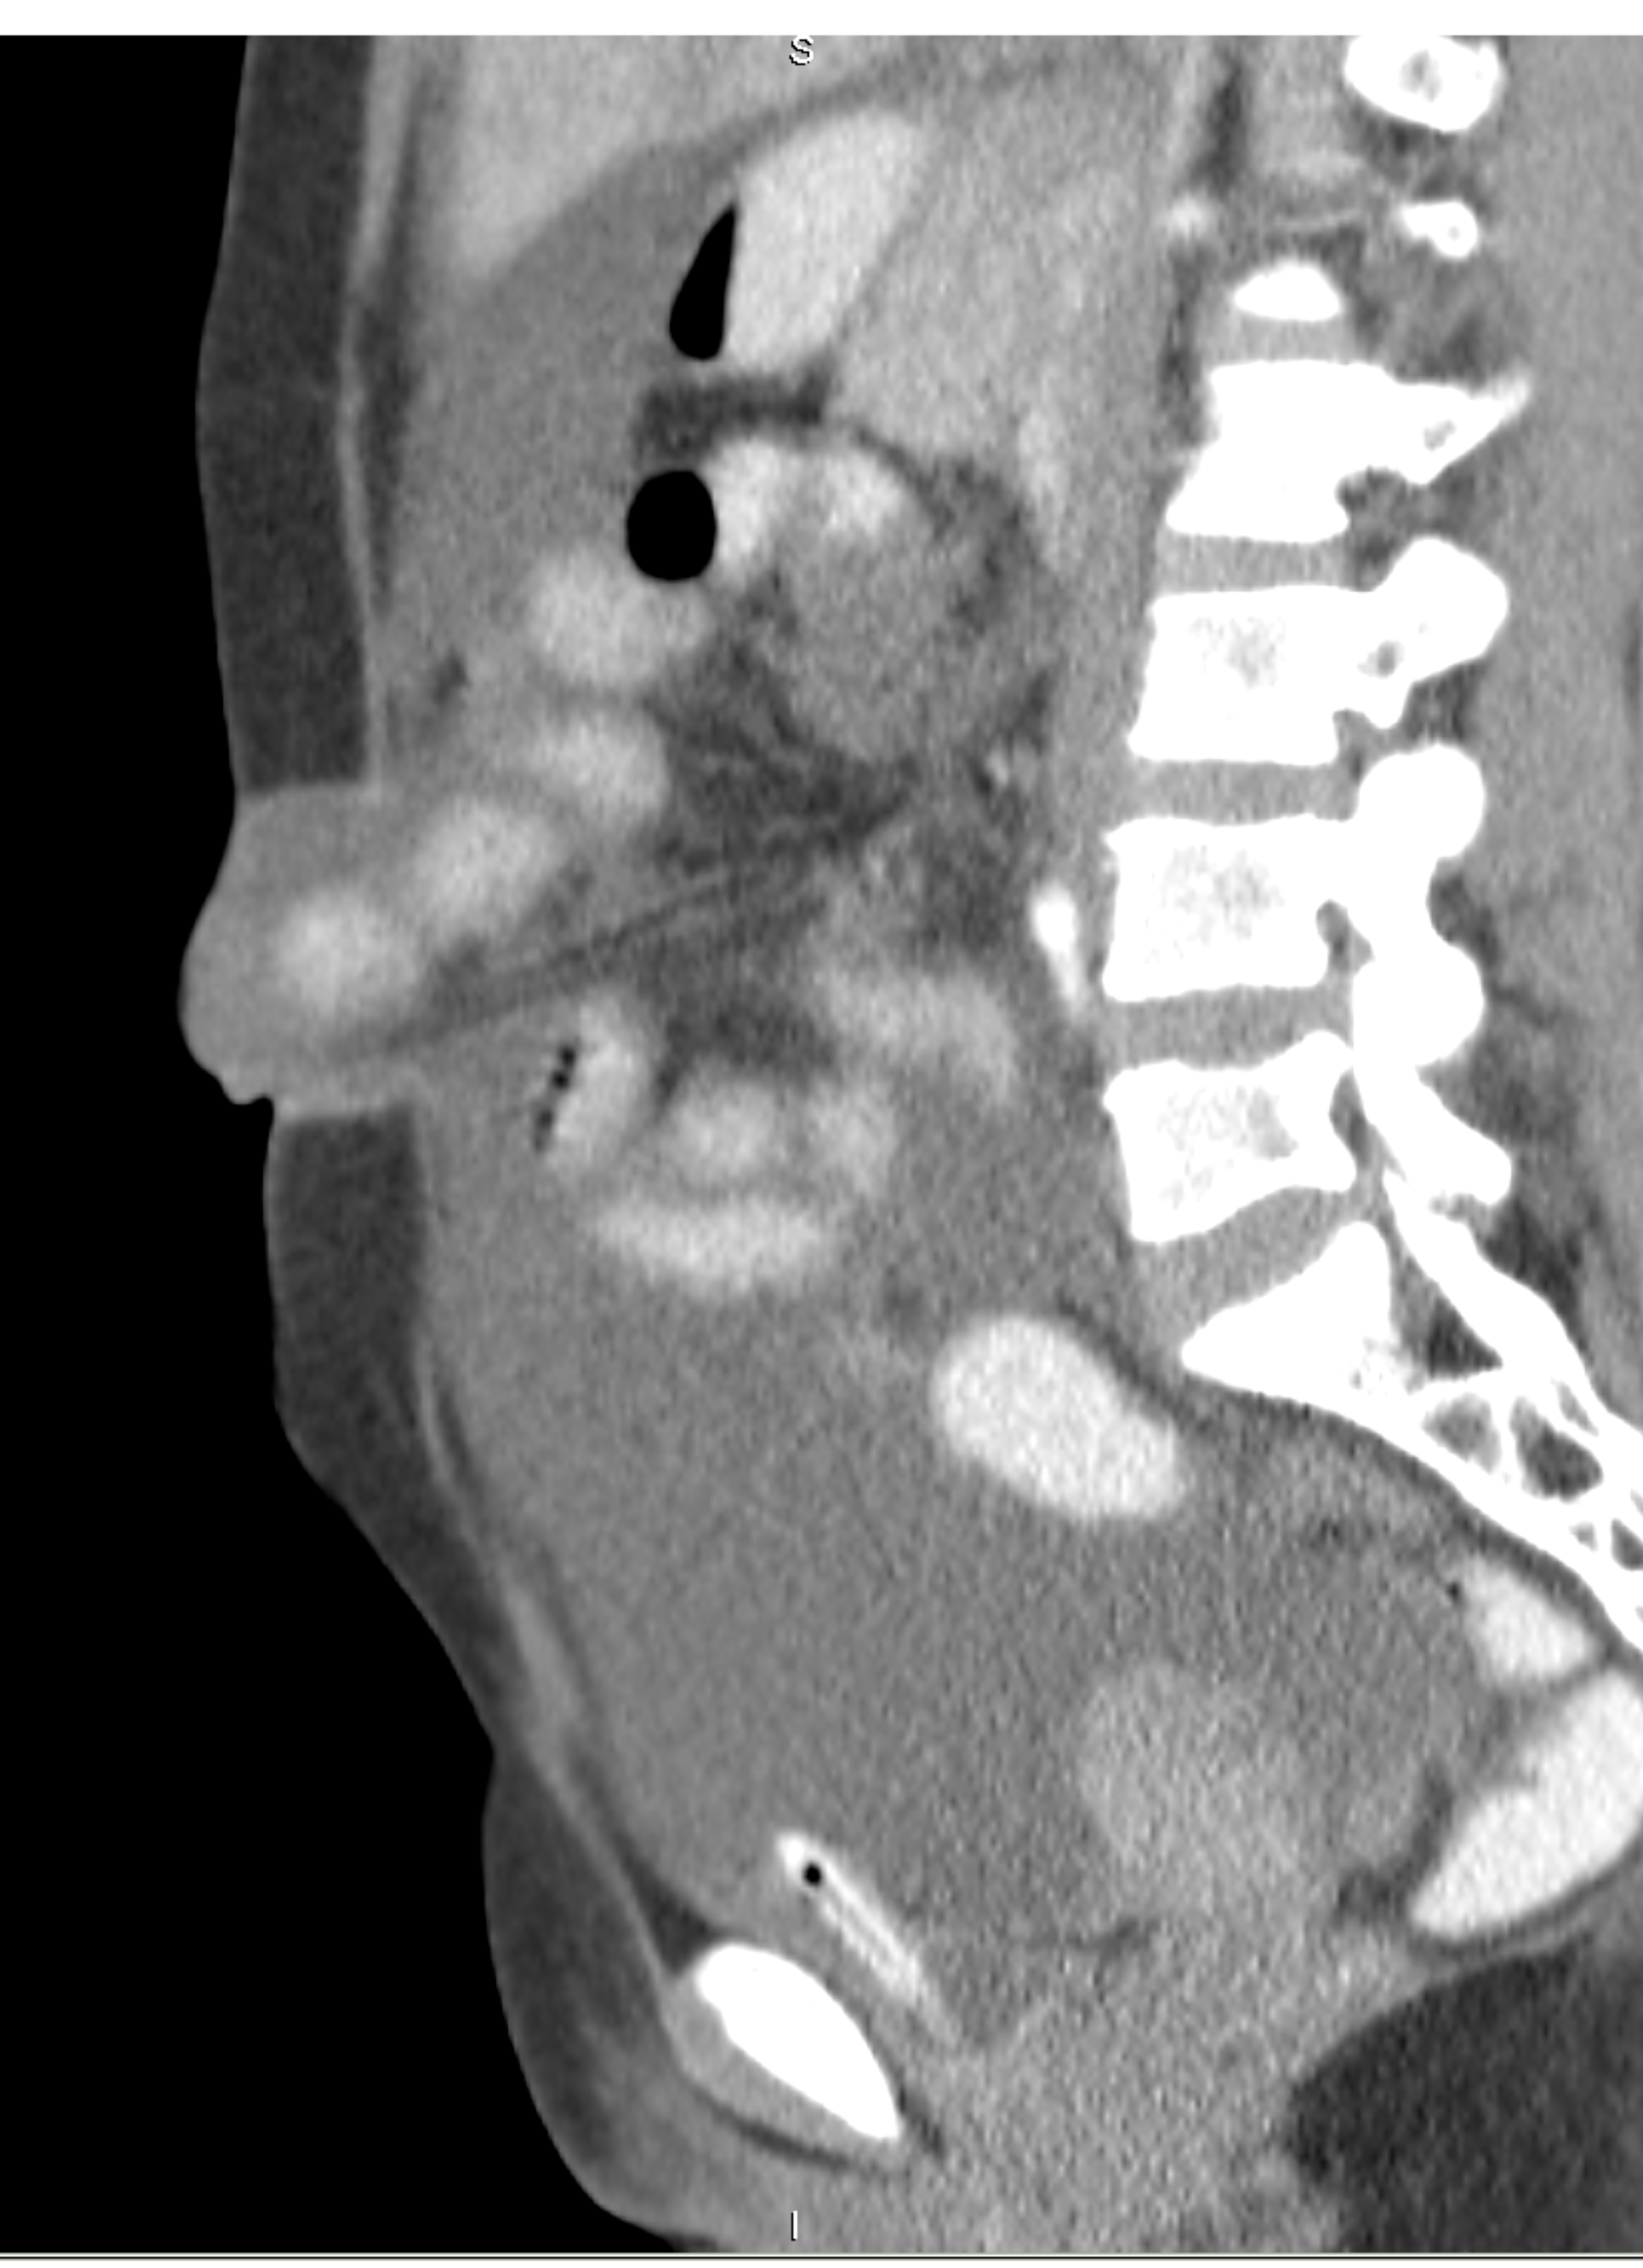

Small bowel obstruction is a common clinical presentation that presents a diagnostic conundrum. Over the last 2 decades, there has been a paradigm shift in the radiological investigation of small bowel obstruction (SBO) and in the indication for and timing of surgical intervention. Cross sectional imaging (predominantly computed tomography) has largely replaced the widespread use of radiographic small bowel follow-through studies as the imaging modality of choice for SBO. This article illustrates the current imaging modalities available for diagnosis of small bowel obstruction. (Full text available online at www.medpharm.tandfonline.com/ojfp) S Afr Fam Pract 2015; DOI: /10.1080/20786190.2014.977052